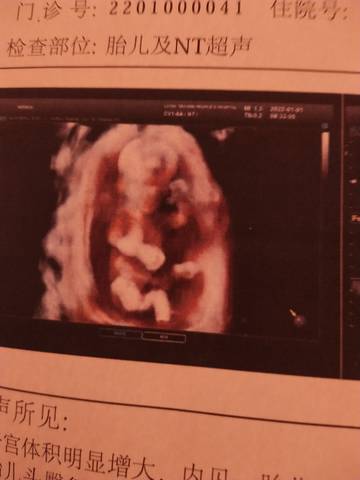

今天刚做的nt,有没有会看的,帮忙看看男宝还是女宝

看不出来,这个单上的数据是很难直接判断男孩还是女孩的哦,其实只要孩子健健康康就好,生下来才最准

你好亲爱的,通过这个来判断男孩女孩是不太准确的哈,我们要给他同等的关爱和呵护,也祝你可以如愿以偿,心想事成。

你好。我们是判断不了男宝宝跟女宝宝的,孕期定期检查,我觉得宝宝健康就好的。祝心想事成 。